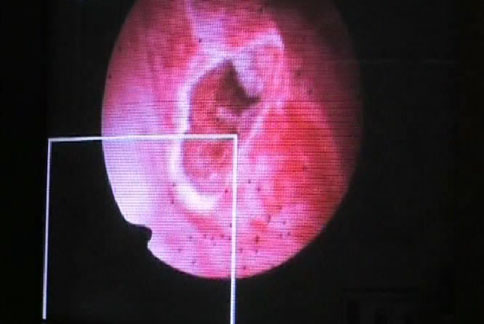

誇張!陰道痙攣難行房 求剪處女膜

【華人健康網 記者黃子倫/台北報導】 201...